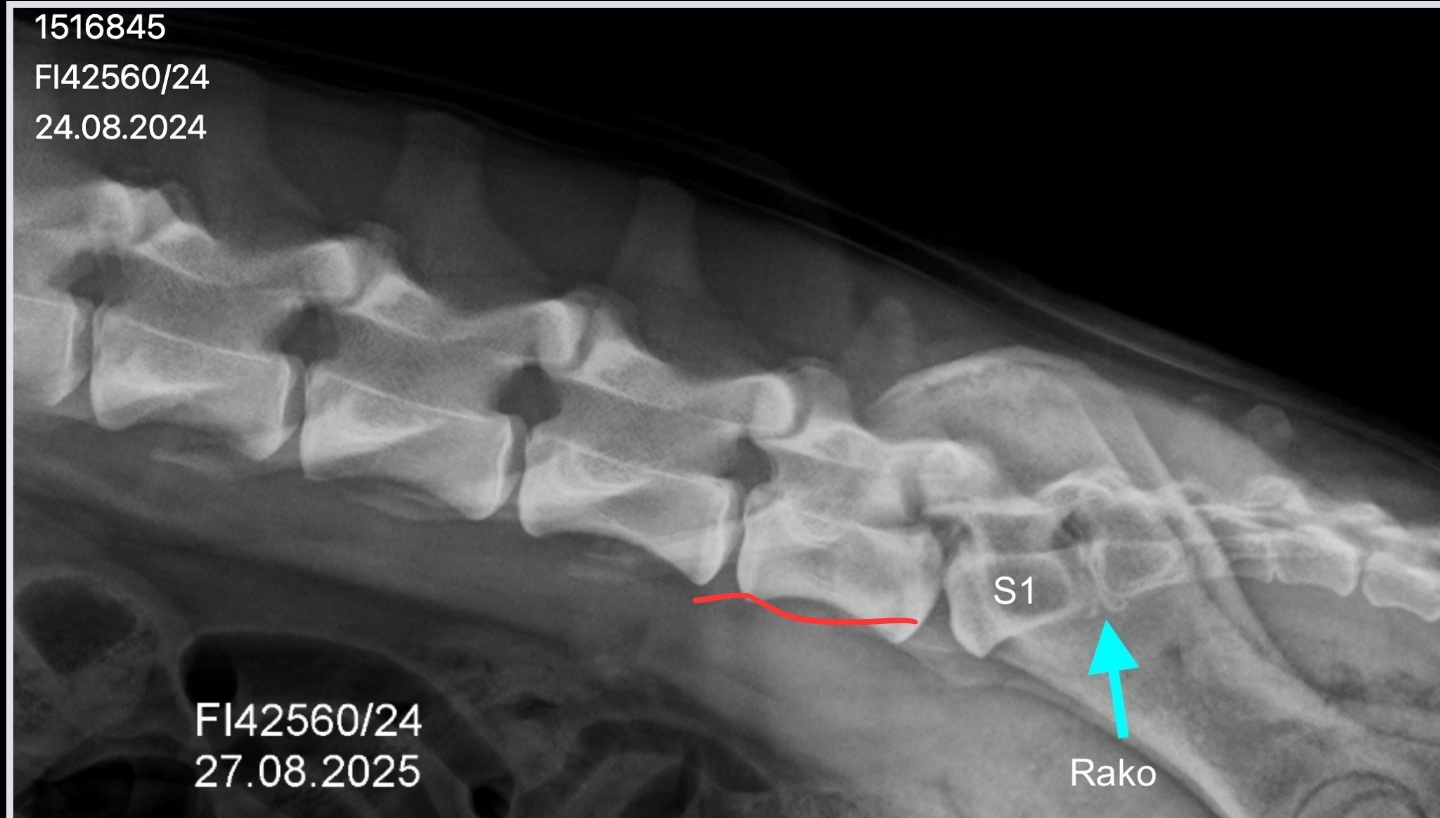

Koiran ensimmäinen ristinikama S1 on epäsymmetrinen ristinikaman ja lannenikaman välimuoto. Se on irti toisesta ristinikamasta ja siinä on epäsymmetrinen poikkihaarakkeet, joista toinen on "vapaa" ja toinen on osittain yhdistynyt suoliluuhun. Lisäksi koiran risti-suoliluunivelet (Sl-nivelet) ovat epäsymmetriset.